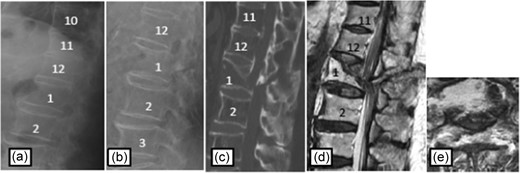

Case 2

Plain radiographs on initial assessment (a) and on admission (b); Sagittal CT image (c) showing the hyperextension fracture at L1 and dislocation of it; MRI T2-weighted image (d, e) showing the severely compressed spinal cord at L1 level.